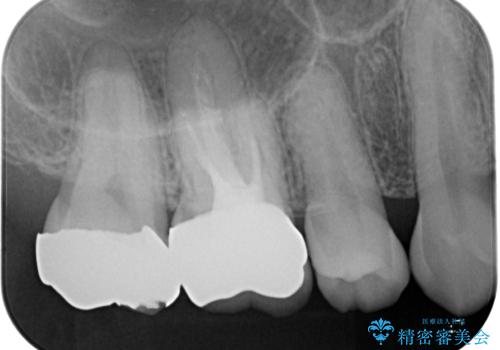

拡大鏡視野下で虫歯の除去を行い、オールセラミッククラウンに適した形に整えました。

型どりはシリコーン印象材にて精密印象をしています。

根管治療を施した歯は割れるリスクが上昇するため、詰め物(インレー)ではなく、被せ物(クラウン)にしなければなりません。

適合もよく、機能的に問題もなく、見た目も満足されていました。